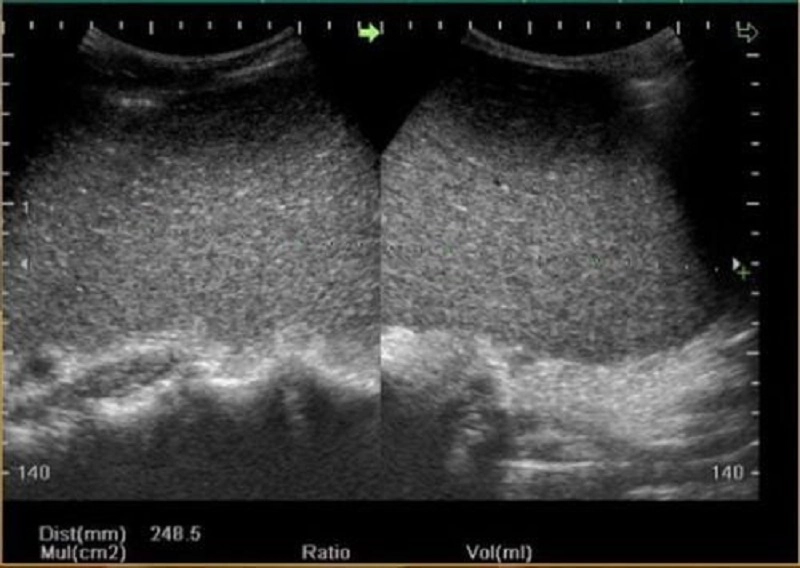

Trong quá trình siêu âm, người bệnh cần để lộ vùng cần kiểm tra và nằm ở tư thế ngửa hoặc nghiêng sang phải theo hướng dẫn của bác sĩ. Bác sĩ sẽ sử dụng đầu dò cong có tần số 3.5 – 5 MHz để thực hiện siêu âm. Trước khi bắt đầu, một lớp gel chuyên dụng sẽ được thoa lên vùng da cần siêu âm và đầu dò để loại bỏ các túi khí, giúp thu được hình ảnh rõ nét hơn.

Người bệnh cần phối hợp với bác sĩ bằng cách điều chỉnh nhịp thở theo hướng dẫn nhằm tối ưu chất lượng hình ảnh. Siêu âm lách được thực hiện với nhiều lát cắt liên tục theo mặt cắt ngang, dọc và đứng để đánh giá toàn diện lá lách từ các góc độ khác nhau, đảm bảo chẩn đoán chính xác.

– Hình ảnh siêu âm lách bình thường: Ở người trưởng thành khỏe mạnh, lách có hình dạng cong lồi lên trên và ra ngoài, lõm xuống dưới và vào trong, với cấu trúc phản âm đồng nhất. Kích thước trung bình của lách khoảng 12 cm (dài), 7 cm (rộng), 3 – 4 cm (dày), và trọng lượng khoảng 150 gram. Kích thước và trọng lượng lách có thể thay đổi theo độ tuổi, tình trạng dinh dưỡng hoặc trong quá trình tiêu hóa.

– Hình ảnh siêu âm lách bất thường: Siêu âm có thể phát hiện các vấn đề như lách to bất thường, dị tật bẩm sinh (lách phụ, không có lách, đa lách), tổn thương khu trú (nang lách, u lách), tổn thương đa ổ (di căn), hoặc chấn thương nghiêm trọng như dập – vỡ lách.